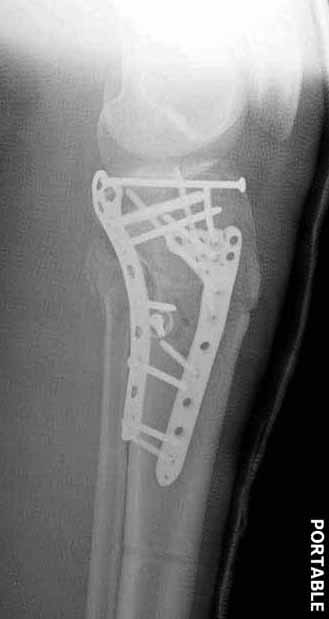

В приложении этапы фиксации Both Column Fx и пластиной Synthes для плеча при переломе медиального мыщелка.

Двухколоннный перелом тибиал плато с вовлечением проксимального диафиза. Внутрисуставной компонент без смещения, и такой перелом можно лечить любым из описанных методов, о которых говорят наши коллеги.

Частая ошибка, когда фиксацию двух колонного перелома проводят одиночной пластиной, т.е с одной стороны, и такая фиксация не удерживает, происходит вторичноое смещение. Необходимо нейтрализовать второй пластиной или дополнительным наружным фиксатором.

Если у вас, кроме пластины, нет другого альтернативного варианта, тогда, учитывая мягкотканые проблемы с наружной стороны, я бы рекомендовал операцию делать в два этапа. Преимущества, сперва репозиция и фиксация перелома с медиальной стороны, а затем, после улучшения состояния мягких тканей, зафиксировать с латеральной стороны. Современные пластины имеют латеральный Jig для перкутанных мини доступов.